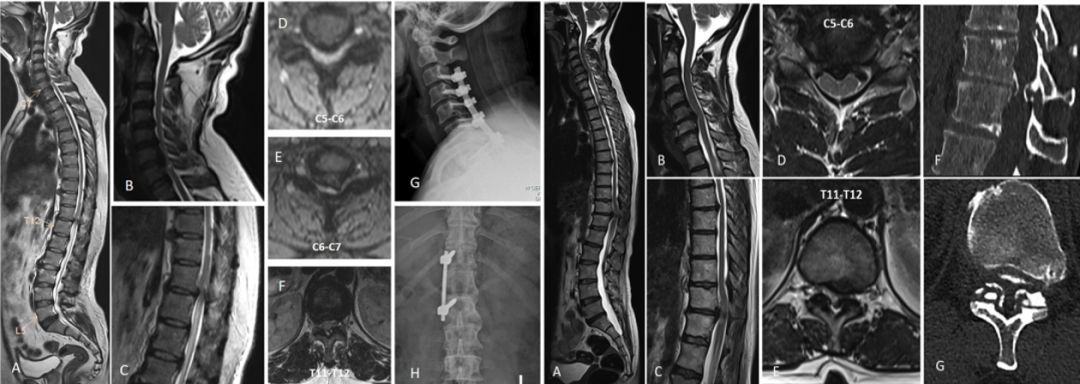

串联性椎管狭窄(Tandem Spinal Stenosis, TSS)是指脊柱的颈、胸、腰三个不同区域的椎管同时发生狭窄,最常见的类型是颈椎和腰椎组合出现,极少数情况下会观察到三重狭窄。作为一种影像学诊断,TSS目前的治疗主要为手术,但具体方案及标准缺乏共识。2026年1月,Rajasekaran教授提出了一种全新的TSS分类及治疗策略,研究结果发表在《The Spine Journal》杂志。

对238例手术患者进行分类,A型186例、B型11例、C型24例和D型17例。A型中A1型58例,A2型97例,A3型7例,A4型24例。B型中B1型6例,B2型5例。C型中C1型20例,C2型4例。所有患者都随访至少2年。患者的平均年龄为62.17±10.91岁,男女比为3:1。

随访结果显示,A1型术前平均Nurick分级从3.8±0.98改善至最终随访时的1.74±0.74,期间仅11例(19%)患者需要另行腰椎减压,平均间隔为8.2个月;A2型平均ODI评分从40.7±13.8改善至15.1±4.8,只有4例患者(4.1%)在期间出现新的脊髓病症状,并接受了颈椎手术,平均间隔为8.8个月;A3型因症状的发展理论上都需要进行二次减压,但出于患者意愿,仅有5例患者(71.4%)另行颈椎减压术,平均间隔8.9个月;A4型有12例患者(50%)接受了分期减压,手术平均间隔为6.9个月。

B1型有3例(50%)需接受二阶段减压,首先进行颈椎减压,然后按计划进行胸椎减压,平均间隔为4.5个月。术前平均Nurick分级从4.6±0.5改善至1.8±0.3;B2型只有1名(20%)患者因持续的脊髓症状需要另行颈椎手术。

C1型有6例(30%)需要另行腰椎手术;而C2型没有患者需要另行胸椎手术。

D型以上肢为主的脊髓病和间歇性跛行患者7例,首先接受颈椎减压,然后进行胸椎和腰椎节段减压,两次手术之间的平均间隔为12.2个月;3例软骨发育不全患者患有脊柱的整体狭窄,2例因寰枢椎不稳在颅颈交界处接受了减压融合术,在2年随访中没有出现明显的胸髓病或神经源性跛行症状。另1例以下肢神经功能障碍为主,接受单次胸腰椎减压治疗;7例有明显腰椎管狭窄的患者接受了分阶段的颈椎和胸椎减压,平均手术间隔为3.2个月,在2年随访中也没有出现神经源性跛行症状。